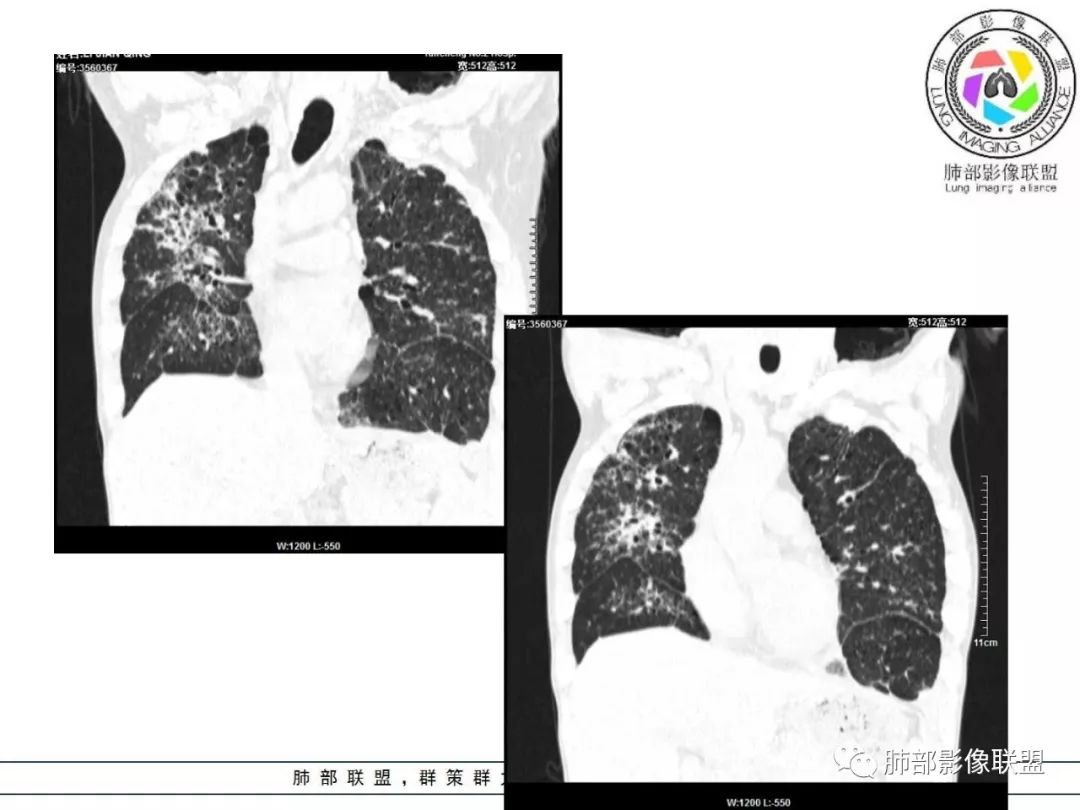

双肺间质性病变,中央间质增厚,胸膜下间质增厚,左侧胸膜肥厚,胸廓变小,肋间隙变窄。

胸部CT:两肺弥漫病灶,磨玻璃影,少许实变,部分累及胸膜,磨玻璃区可见囊?少许胸腔积液,两肺可见结节,支气管血管束增粗,小叶间隔增厚,支气管走形有扭曲扩张,可见纤维化。气肿、大泡。考虑:感染性病变,PCP?查下HIV,CD4,G等。鉴别结核、结缔组织病肺浸润。

55多男性,发热为主诉,体温38℃-39℃多,午后及夜间发热为主,峰值40℃,伴黄痰,CRP高,血糖正常,胸部CT:两肺弥漫病灶,磨玻璃影,少许实变,部分累及胸膜,两肺可见结节,似可见树芽,支气管血管束增粗,小叶间隔增厚,见肺气肿、大泡。考虑感染性病娈,肺结核可能性大。

患者中年男性,发热1月,体温38℃-39℃,峰值40℃,无畏寒、寒战,伴黄痰,CRP升高明显,降钙素原稍升高,血沉、血糖正常。胸部CT:两肺弥漫病变,磨玻璃影+点片渗出,部分累及胸膜,磨玻璃区边界清楚,少许胸腔积液,两肺支气管血管束增粗,小叶间隔增厚,部分支气管走形有扭曲扩张,可见肺气肿、右肺尖肺大泡及部分纤维化改变。综合考虑:感染性病变。结核或PCP可能性大,鉴别风湿免疫、结缔组织疾病肺浸润和腺癌等恶性病变。

胸部CT:两肺弥漫病灶,中央间质分布为主,部分位于胸膜及叶间裂旁,磨玻璃影,斑片影,部分实性结节,肺气囊,支气管血管束增粗,小叶间隔增厚,叶间裂不均匀增厚,支气管走形有扭曲扩张,可见纤维化、气肿、大泡。考虑:LIP加MALT。鉴别PLCH、PCP、结核、结缔组织病肺浸润。

病灶呈片状磨玻璃密度影,呈典型的烟花征。磨玻璃影密度偏高,有网结节样改变,与正常肺实质分界清楚,且常见相对高密度的勾画。

病变一般沿血管支气管束分布或小叶分布,一般上肺多于下肺(这与常见继发性肺结核分布相若)。

2. 肺气肿背景(小叶中心性肺气肿);双肺多发病灶整体沿血管支气管束及胸膜下分布,以上叶及下叶背段分布为主,有实变及GGO,边界清楚,有树芽,小叶间隔及中央间质增厚,叶间裂见到多发结节,部分支气管不规则牵拉扩张,提示病灶纤维化明显,结合临床病史,考虑病灶为间质性感染,肺门及纵隔内有钙化淋巴结,小叶间隔结节,考虑淋巴道增值性疾病可能,综合常规要怀疑间质性肺结核。